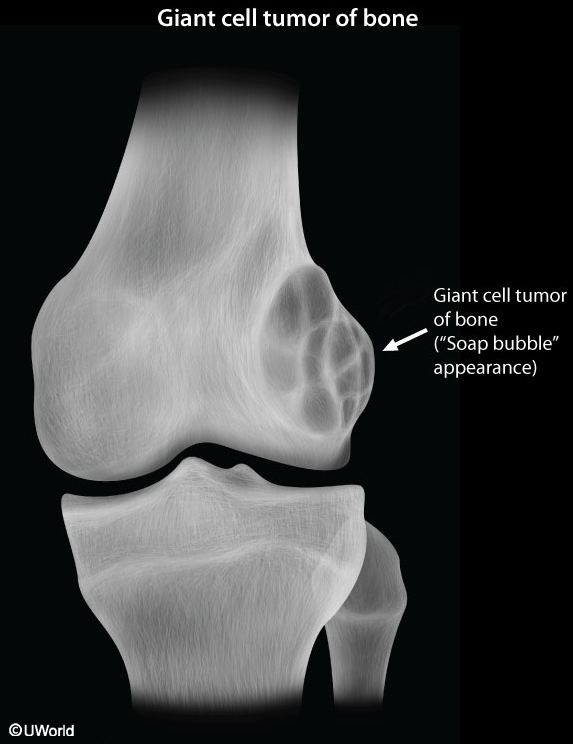

Giant Cell Tumor

This patient's x-ray findings of an expansile and eccentric lytic area ("soap-bubble" appearance) are highly suggestive of giant cell tumor of bone (GCTB). GCTB is a benign and locally aggressive skeletal neoplasm seen in young adults. Patients usually present with pain, swelling, and decreased range of joint motion at the involved site. Nearly 10%-35% of affected patients experience pathologic fractures due to thinning of the bone cortex in weight-bearing areas.

GCTB typically presents on x-ray of the epiphyseal regions of the long bones, most commonly the distal femur and proximal tibia around the knee joint. Magnetic resonance imaging can show the tumor containing both cystic and hemorrhagic regions. Pathology typically shows sheets of interspersed large osteoclast giant cells that appear as round-to-oval polygonal or elongated mononuclear cells. Surgery (eg, intralesional curettage with or without bone grafting) is first-line treatment for GCTB.